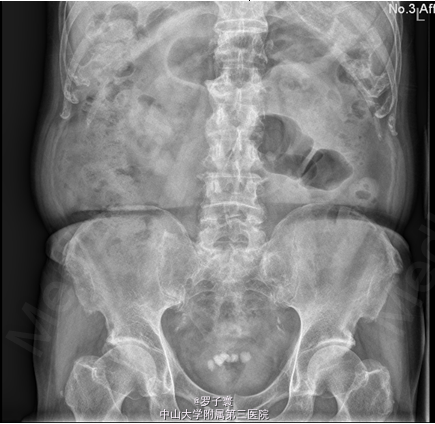

者入院完善相关检查:尿常规提示红细胞计数增高(RBC44个/ul),生化、凝血、术前筛查、肿瘤三项、PSA两项、性激素六项、血常规未见明显异常。泌尿系彩超:双肾集合系统回声增多,不排除小结石;双侧输尿管未见扩张;膀胱多发结石;前列腺增大,前列腺钙化斑;双侧精囊超声检查未见明显异常。腹部平片:考虑膀胱多发结石。

患者排除相关禁忌症于2014-06-04行经尿道膀胱碎石取石术。腰硬麻下,取截石位,手术部位常规消毒铺巾。 F27经皮肾镜连接监视系统,直视下进入膀胱,见后尿道前列腺中度增生,膀胱颈明显抬高,膀胱内小梁小房,可见憩室,见黄褐色膀胱结石5个,约2.1×1.2cm,表面粗糙,不规则形,褐色,双侧输尿管开口无水肿、狭窄等,接超声碎石系统,经皮肾镜进入膀胱,击碎结石,将碎石吸出,收集碎石送检,手术过程顺利,术中出血少,未输血,术后病人安返病房。术后予抗生素预防感染、补液等对症治疗,于2014-06-07拔除尿管。